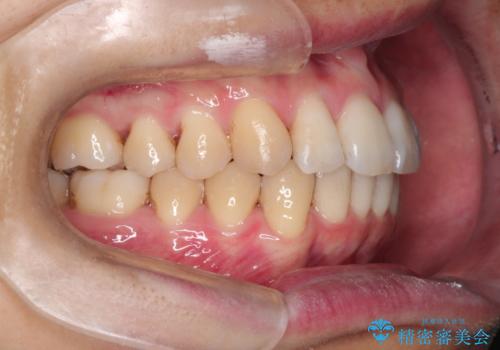

前歯の凸凹をきれいにしたい。インビザラインによる治療

- 前歯の凸凹を主訴に来院された患者様です。

インビザラインにて治療を行いました。